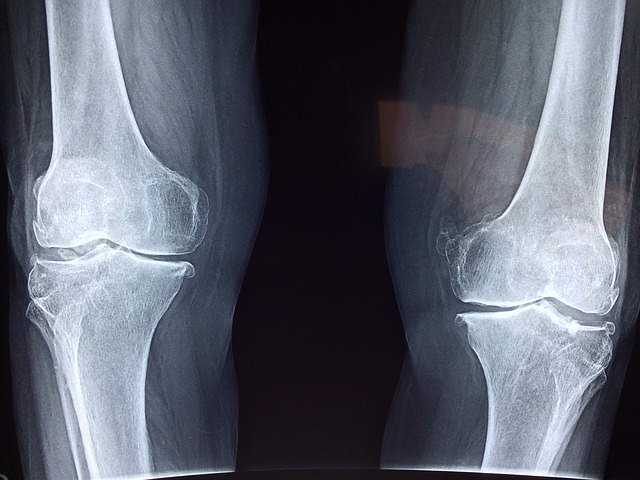

- 항염증 효과: 우슬의 사포닌 성분은 체내의 염증 반응을 조절하여 염증을 감소시키는 데 도움을 줍니다. 이로 인해 관절염, 강직성 척추염 등 염증성 질환의 증상 완화에 기여할 수 있습니다.

- 골다공증 예방: 연구에 따르면, 우슬은 뼈의 밀도를 증가시키고 골 손실을 방지하는 데 도움을 줄 수 있습니다. 이는 골다공증이나 다른 뼈 관련 질환을 예방하거나 관리하는 데 유익할 수 있습니다.

- 글루코사민 및 콘드로이친: 관절 건강을 지원하는 보충제인 글루코사민과 콘드로이친은 우슬과 함께 섭취할 경우, 관절의 윤활과 회복을 돕고 통증을 감소시키는 데 도움을 줄 수 있습니다.